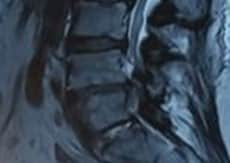

After obtaining informed consent, the patient was taken to the operating theatre. Antibiotics were administered by peripheral venous access to prevent infection before intradiscal PRP injection. PRP was made by the department of transfusion medicine, ShSMCH, and the platelet count was more than 1000000/ml. The patient was placed in a prone position on the X-ray operating table, and the L4-5 level was identified by counting vertebrae from X-ray images. With all aseptic precautions, the skin was infiltrated with 1% lignocaine. Then, a spinal needle (22-gauge, 150mm) was inserted into the nucleus pulposus (NP) of the L4/5 disc in the anteroposterior (AP) and lateral views under intermittent fluoroscopy. Approximately 2 mL of PRP was slowly injected through a syringe into the disc. After the procedure, the patient was observed in the post-operative ward for about an hour and found uneventful. The patient was advised to do activities of daily living and physical activity, such as exercise, at 7 days and 1 month postinjection, respectively. She was also advised not to take steroids and non-steroidal anti-inflammatory drugs (NSAIDs) for about 1 month, except in the case of particularly severe pain (VAS scores of 8 points or more). Follow-up surveys, including VAS, RMDQ, and any side effects, were carried out by phone at 1 week, 1 month, 3 months, 6 months, and 12 months following intradiscal PRP injections. Quality of life by SF-12 was measured after 1 month, 6 months, and 12 months. Subsequently, a follow-up MRI of the lumbar spine was done after 6 months of injection. Figure 1 shows the Modic change before and after PRP injection. A decrease in high signal intensity on T2WI was seen after PRP injection in the intervertebral disc at the L4/5 disc.

MRI shows modic change before (a,b) and after (c,d) PRP injection

Figure 1: MRI shows modic change before (a,b) and after (c,d) PRP injection

The process of Modic change in our patient was somehow reversed by PRP injection. This autologous platelet-rich plasma mimics the physiological repair process by releasing autologous growth factors (GFs) and creating a transient biological matrix. It can be considered that PRP treatment could stimulate the endogenous repair machinery and induce the healing of damaged spinal components to ultimately restore disc and vertebral bone homeostasis and an improvement in the functional anatomy of the end plate.[20] It is difficult to determine whether Modic type 1 is the cause of LBP. Discography may be necessary to diagnose Modic change accurately as the cause of LBP. However, discography, an invasive test, was not performed in this study because a significant association was established between MC and LBP.[25]

Only a few reports demonstrate MRI improvements in disc degeneration and Modic change after PRP treatment. As MRI provides more detailed information, the case presented here shows appreciable MRI improvements in terms of decreasing high-signal intensity on T2WI after 6 months of PRP therapy.[20,25] Other modalities like intradiscal steroid injections, anti-tumor necrosis factor (TNF)-α antibodies, and antibiotic administration, have been reported to have short-term efficacy in Modic change, but long-term results are unknown. Albert et al. treated patients with Modic type I with antibiotics for 100 days and reported that the VAS of patients with LBP improved from 67 to 37 mm after 1 year.[27]